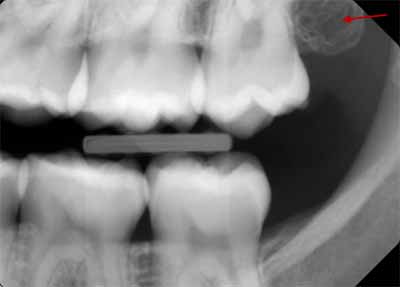

しかし、放射線源が患者から少し離れた位置で回転するパノラマX線撮影では、この拡大率の違いが見られます。舌がその例です。顎の画像撮影では、舌は放射線源の近くにあるため、広い範囲にわたって撮影されます(図29を参照)。

デンタルX線写真と同様に、上顎切歯より上方に描かれた鼻の軟組織部分の輪郭を見ることができます。また、外耳は頸椎と頸椎枝の間に丸みを帯びた、わずかにエックス線不透過性の構造体として描かれていることもわかります(画像28を参照)。

ゴーストはパノラマ画像を撮影するときに発生する歪みの1つであり、画像を確認するときに考慮する必要があります。簡単に説明すると、ゴースト画像とは、画像が撮影されたときに、画像化された顎の反対側にあった構造の画像です。これらの構造は、画像の反対側にぼやけて拡大されて表示されます。

ゴーストの最も明確な例の1つは、下顎底です。たとえば、下顎の右側を撮影する場合、X線放射は下顎の左側も通過する必要があります。この場合、下顎の左側は焦点レイヤーの外側にあるため、この構造の不明瞭なゴースト画像が右側の画像に重なって表示されます。もう1つの例は頸椎です。頸椎の場合、前歯が描かれると顔の前部と顎の上にゴースト画像が作成されます(画像30を参照)。これらのゴースト画像により、パノラマX線画像での診断が困難になります。